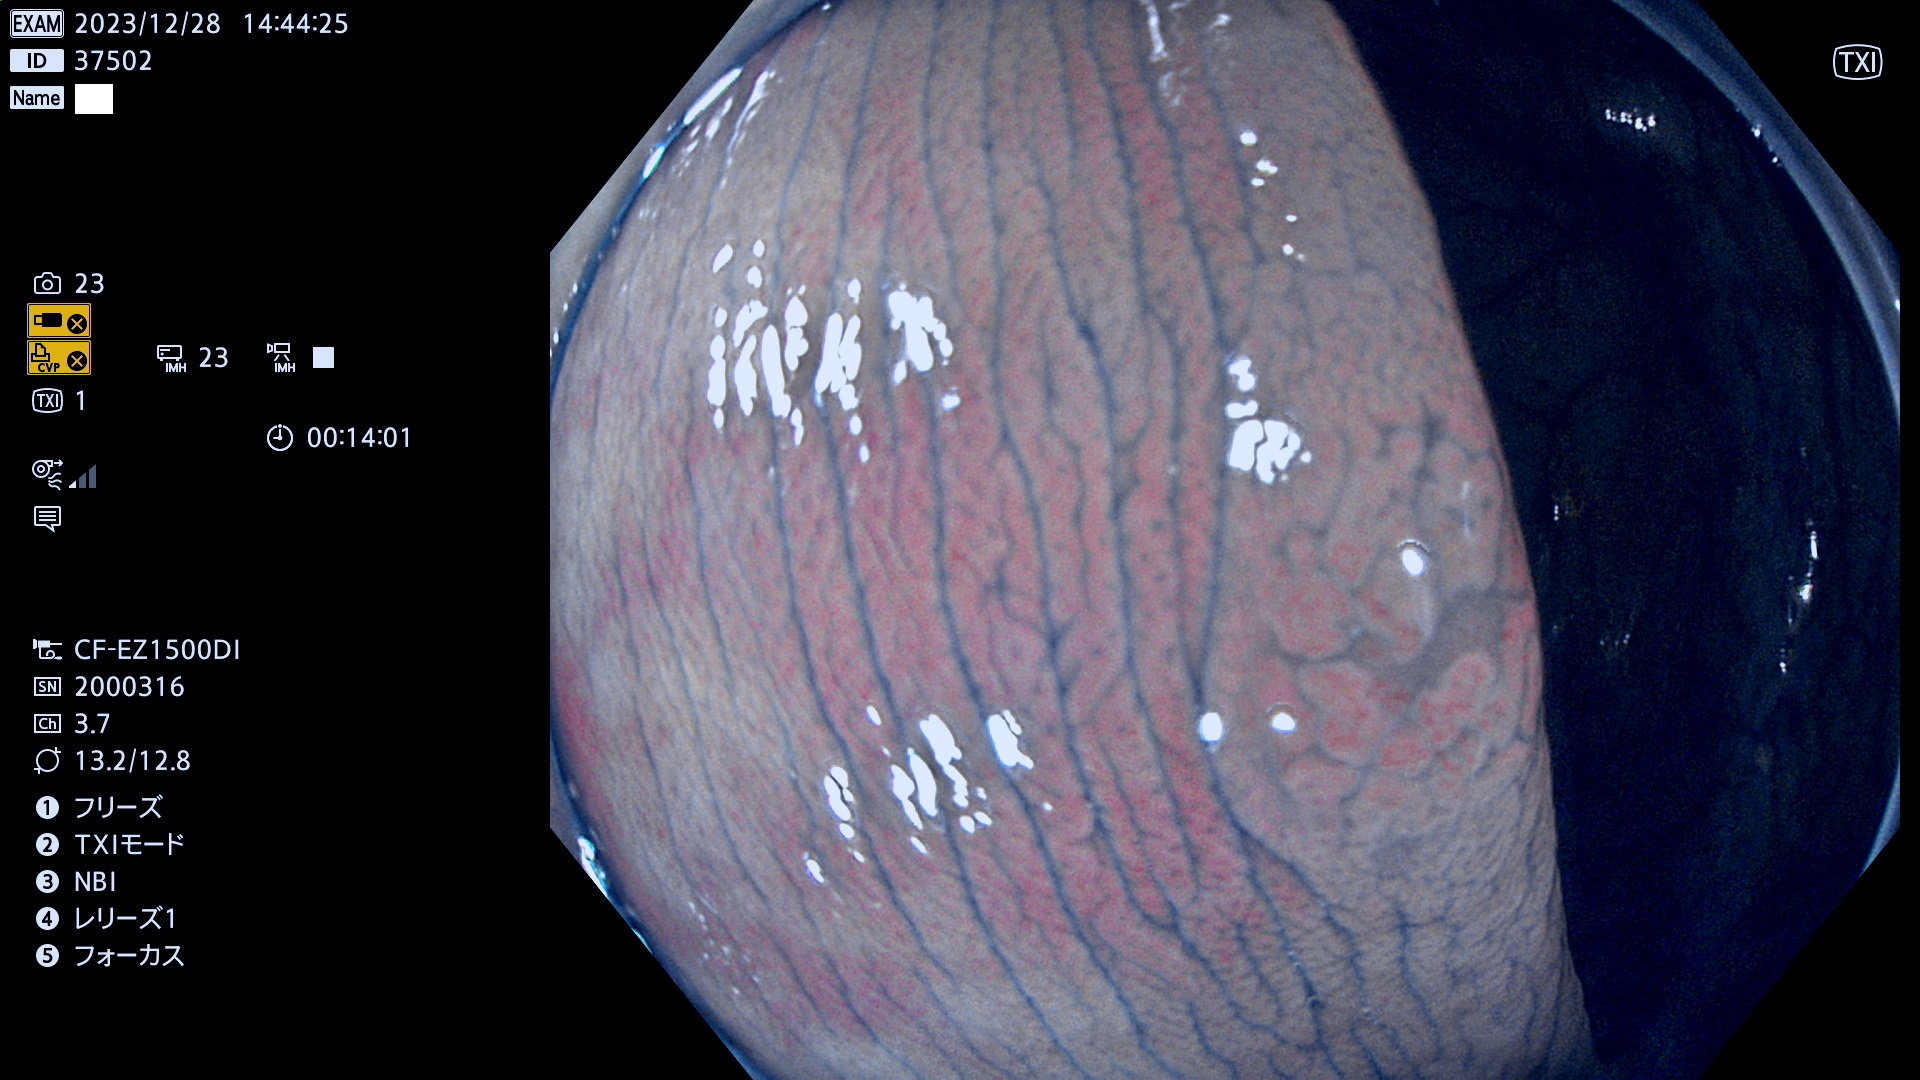

表面型腺腫(Flat Adenoma)の中で、完全に平坦な物をUb、陥凹している物をUcと呼びます。平坦隆起型(Ua)よりも、発見が難しく危険な病変です。

毎週の検査(木・金・土・日)に発見されたUb、Uc型・腺腫を、その週の日曜の夜にUPし1週間、提示します。

抽出の対象期間 2023年12月28日(木)〜12月31(日)の4日間(48件の検査)7件